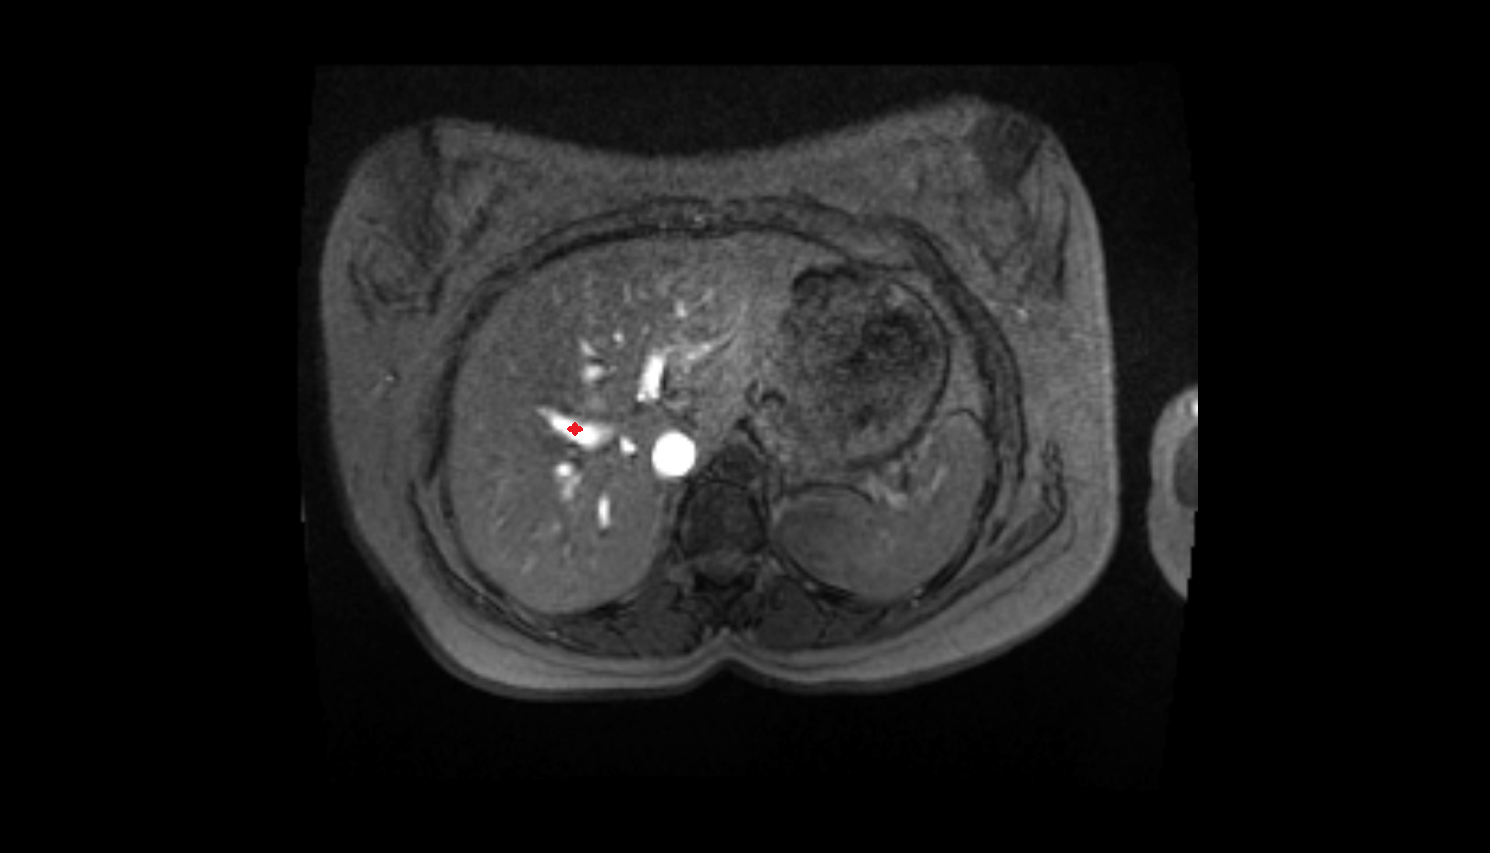

- Left lobe of liver

- Right lobe of liver

- Liver

- Spleen

- Pancreas

- kidneys

- Right kidney

- Left kidney